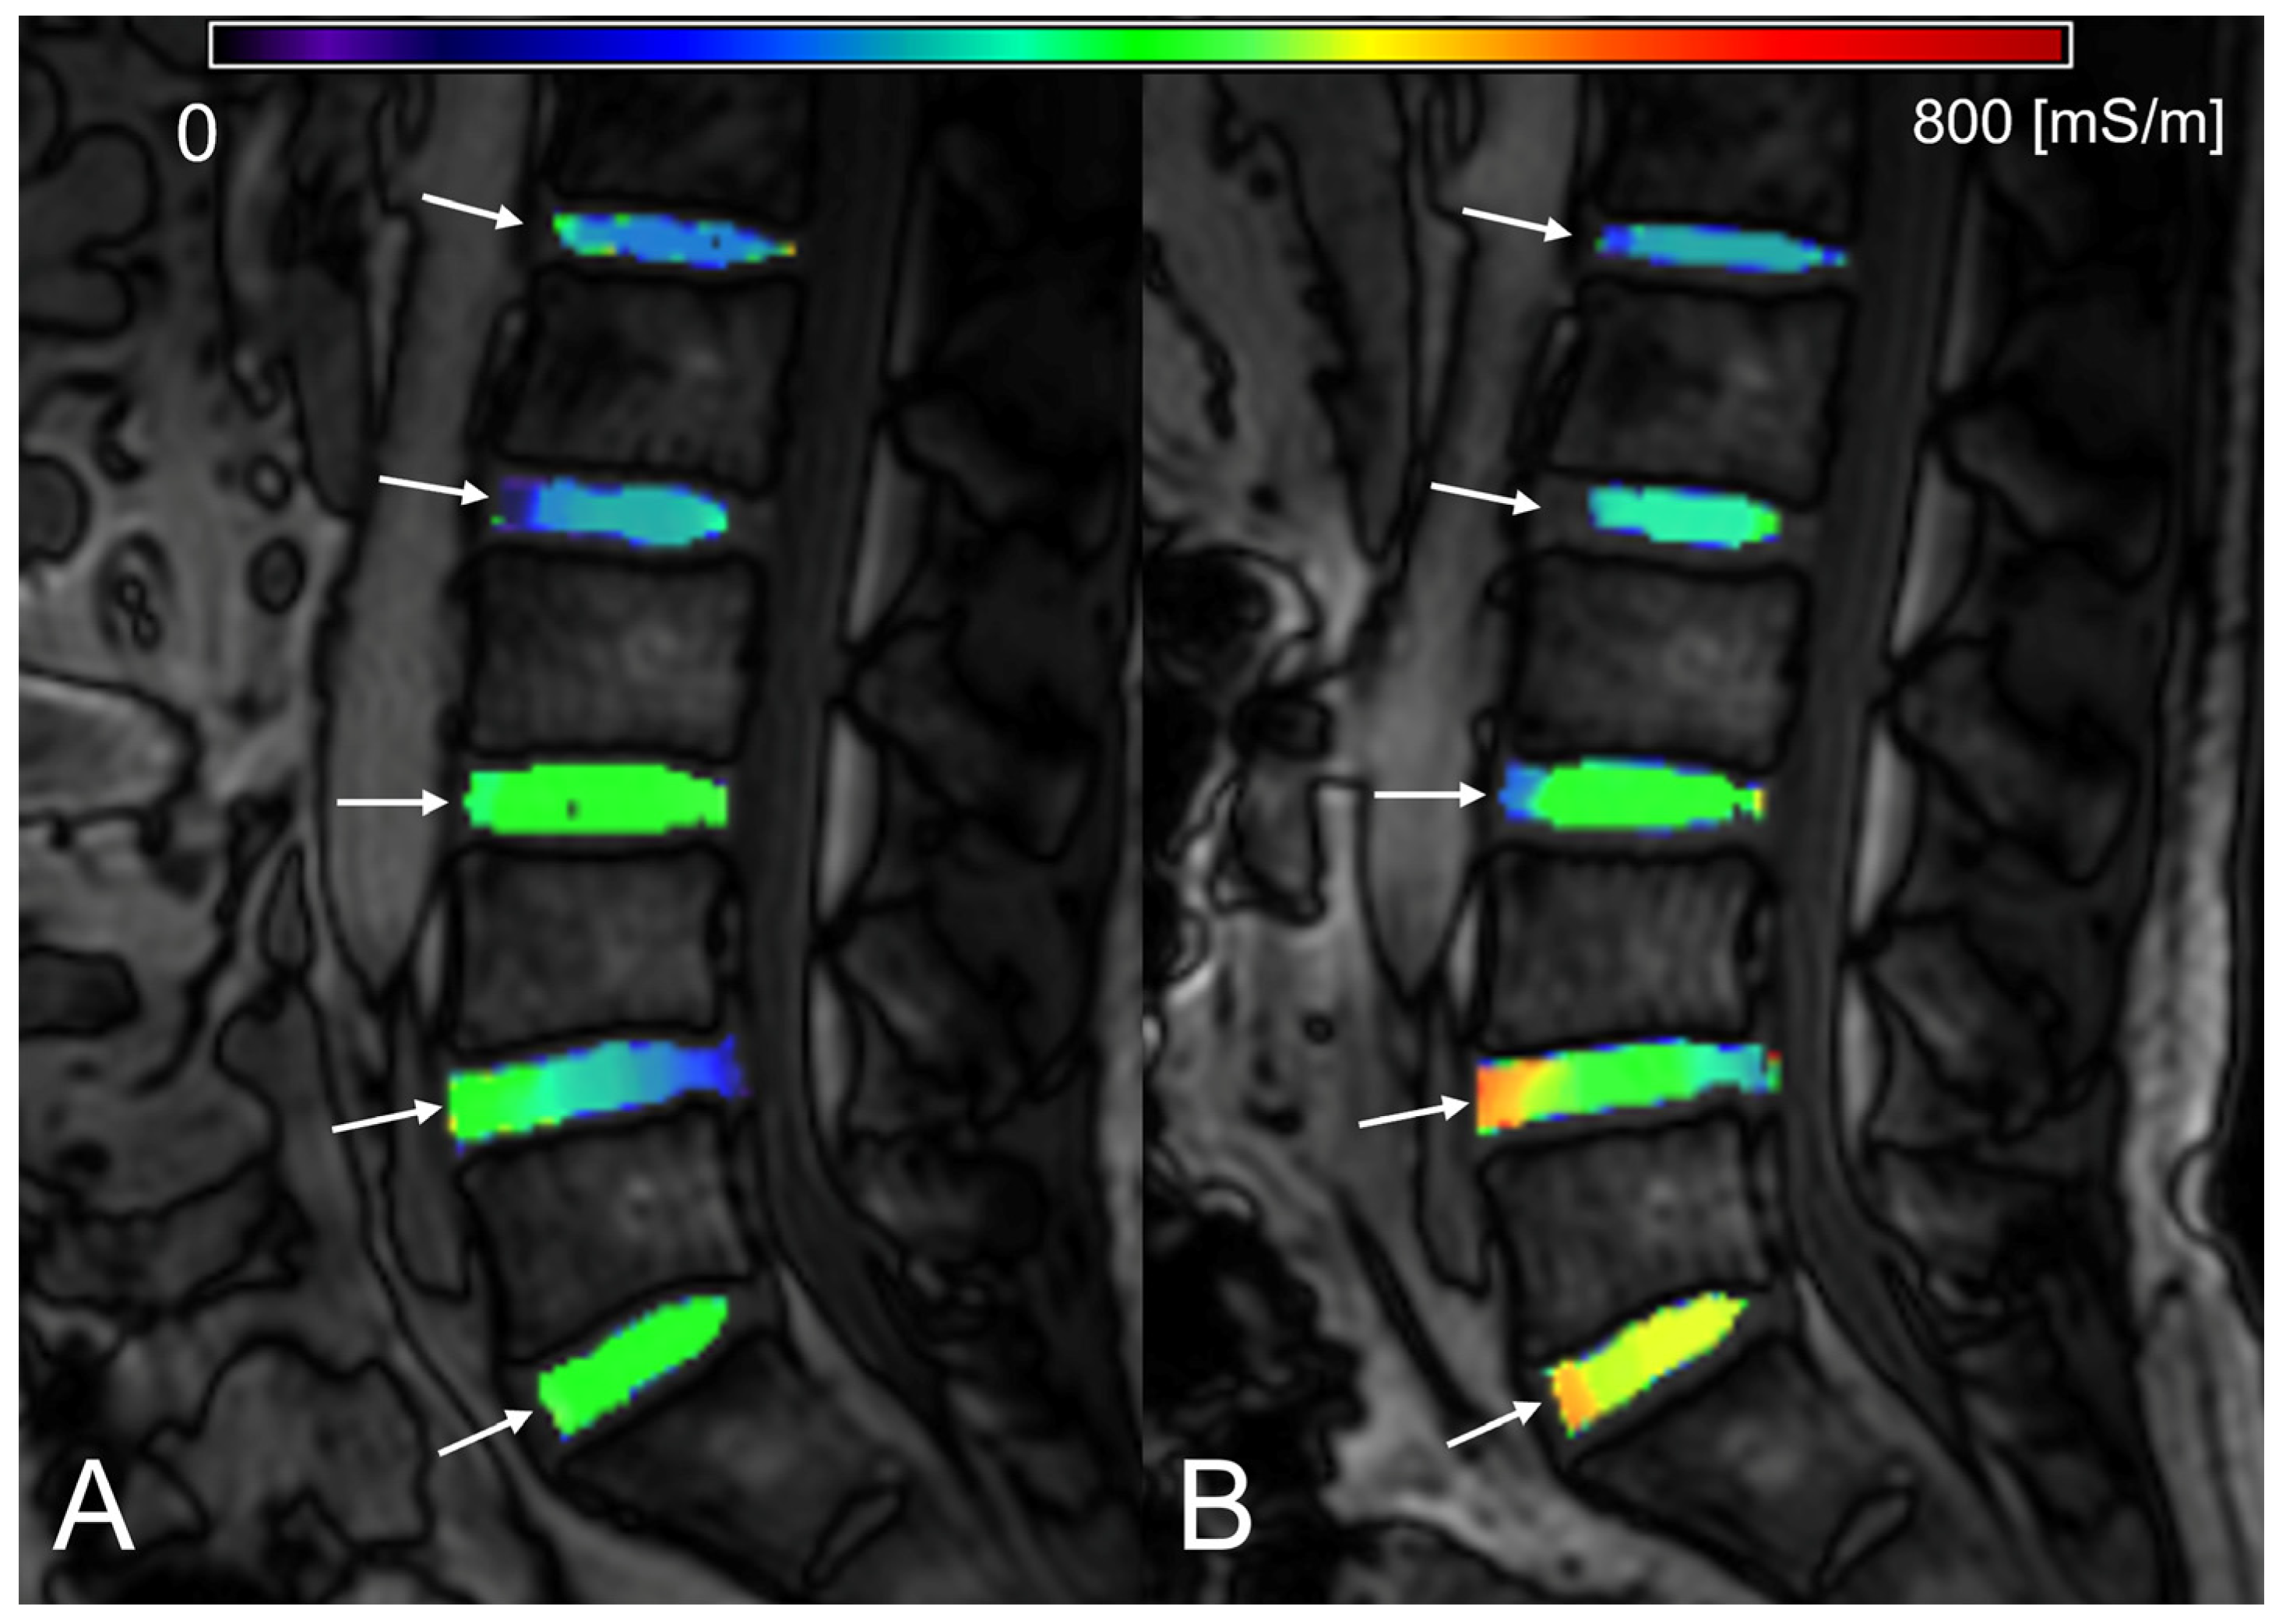

2.5. Region-of-Interest Setup and Measurements